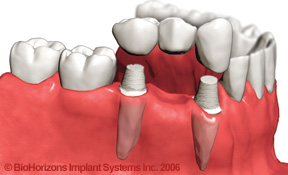

2 Missing Teeth

The First Implant Placed

2 Implants Placed

2 Implant Supported Crowns